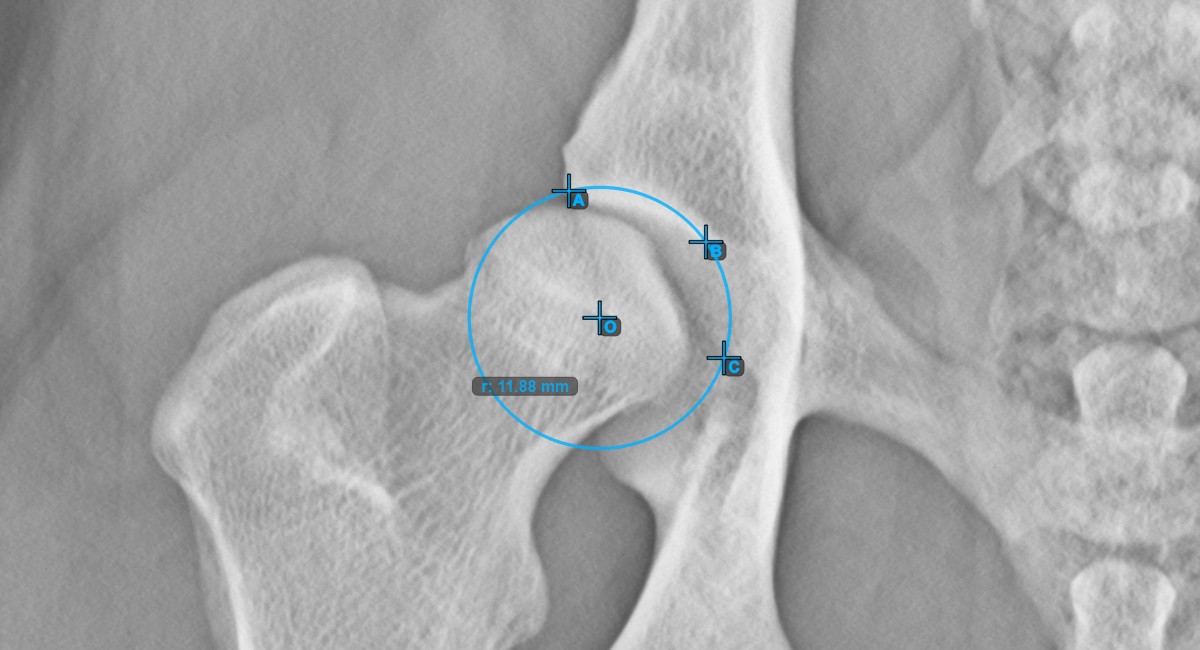

Start the measurement by marking the three points on the articular surface of the Acetabularis.

Designate the left or right Acetabularis bone and mark the three points along the articular surface. A circle will be automatically constructed based on the three placed points.

The image below represents a typical placement of the three points on the articular surface of the Acetabularis.